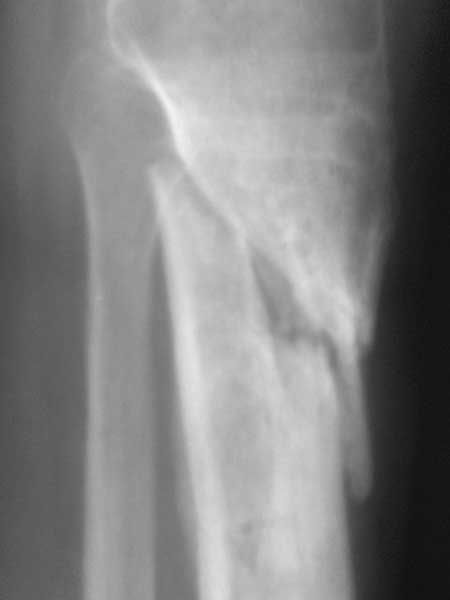

Re: Ложный сустав б/ берцовой с инфицированием

Спасибо за обсуждение.Отправил остальные R, изиняюсь за качество.

2.Возникновение раны склонен связывать с эпизодом спицевой инфекции нашедшей себе "уютное место" в плохо васкулизированных интерпонироанных мягких тканях между отломками. Я думаю что нет разницы где ложный сустав( в губчатой или др.) -он будет если там интерпозиция.

3.Перелом на 2 уровнях, есть искривление костно-мозгового канала. Проксимальный отломок короткий.